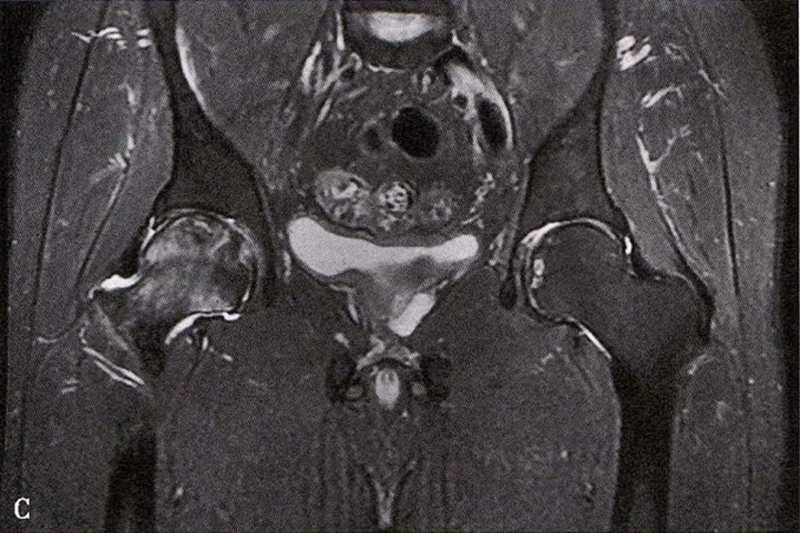

(2)MRI检查 MRI检查是早期诊断股骨头坏死最具特异性、灵敏度的检查方法。当怀疑有股骨头坏死,而X线片无明显异常时,应行MRI检查。诊断时可根据髋关节X线、MRI显示的坏死面积和塌陷程度进行ARCO分期。

冠状面及横断面MRI图像

MRI示双侧股骨头坏死,冠状面显示右侧股骨头坏死(图A、C),横断面显示双侧股骨头坏死(图B、D);T1加权像(图A、B)显示硬化带为低信号,T2加权像(图C、D)显示右侧骨坏死硬化带外围高信号的骨髓水肿,左侧无骨髓水肿。